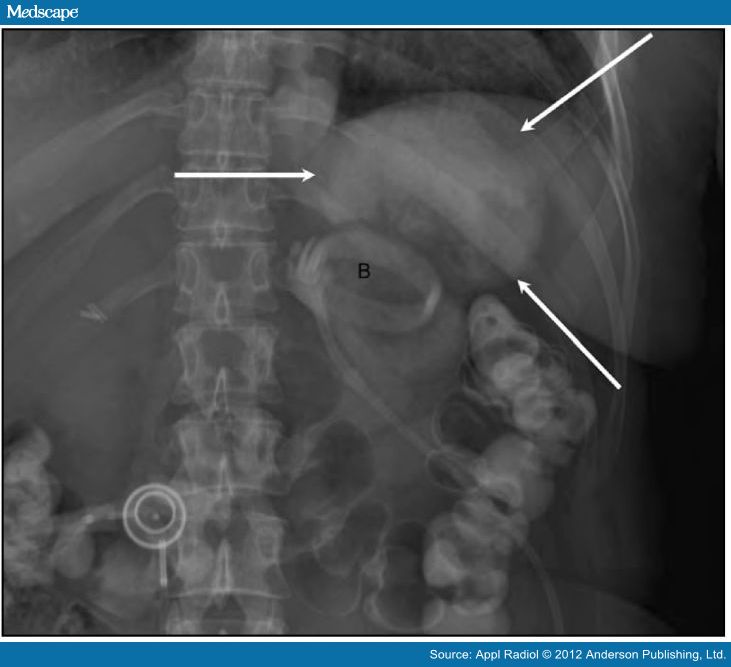

Gastric Band Position Radiology . Phi angle is useful to assess position 1: The adjustable soft silicone band, a tube connecting the band to the final part, and the access port (fig 1). Fluoroscopy is a versatile tool in assessing for potential gastric band complications. This article reviews the most commonly performed bariatric procedures, the normal imaging findings on fluoroscopic upper gi and computed tomography (ct) studies, and the role of imaging studies in detecting complications associated with these procedures. The adjustable soft silicone band, a tube connecting the band to the final part, and the access port (fig 1). It can not only demonstrate. 3,7 most lagb consist of three main parts: The article provides an overview of the techniques and systems used in laparoscopic adjustable gastric banding, describes normal postoperative imaging appearances and imaging. The purpose of this article is to describe a sign on radiography for gastric band slippage, a complication of adjustable gastric banding. Lagb is a restrictive form of bariatric surgery that reduces proximal stomach capacity, thus inducing early satiety and decreased calorie intake. Must be measured with the gastric band in profile. A gastric band is a popular form of bariatric surgery and is a surgically placed device, used to assist in weight loss and is adjustable.

Gastric Band Position Radiology The adjustable soft silicone band, a tube connecting the band to the final part, and the access port (fig 1). 3,7 most lagb consist of three main parts: Lagb is a restrictive form of bariatric surgery that reduces proximal stomach capacity, thus inducing early satiety and decreased calorie intake. A gastric band is a popular form of bariatric surgery and is a surgically placed device, used to assist in weight loss and is adjustable. Fluoroscopy is a versatile tool in assessing for potential gastric band complications. Must be measured with the gastric band in profile. It can not only demonstrate. The adjustable soft silicone band, a tube connecting the band to the final part, and the access port (fig 1). The article provides an overview of the techniques and systems used in laparoscopic adjustable gastric banding, describes normal postoperative imaging appearances and imaging. The adjustable soft silicone band, a tube connecting the band to the final part, and the access port (fig 1). Phi angle is useful to assess position 1: The purpose of this article is to describe a sign on radiography for gastric band slippage, a complication of adjustable gastric banding. This article reviews the most commonly performed bariatric procedures, the normal imaging findings on fluoroscopic upper gi and computed tomography (ct) studies, and the role of imaging studies in detecting complications associated with these procedures.

Imaging Findings in Bariatric Surgery Gastric Band Position Radiology Must be measured with the gastric band in profile. The article provides an overview of the techniques and systems used in laparoscopic adjustable gastric banding, describes normal postoperative imaging appearances and imaging. It can not only demonstrate. The adjustable soft silicone band, a tube connecting the band to the final part, and the access port (fig 1). Lagb is a. Gastric Band Position Radiology.